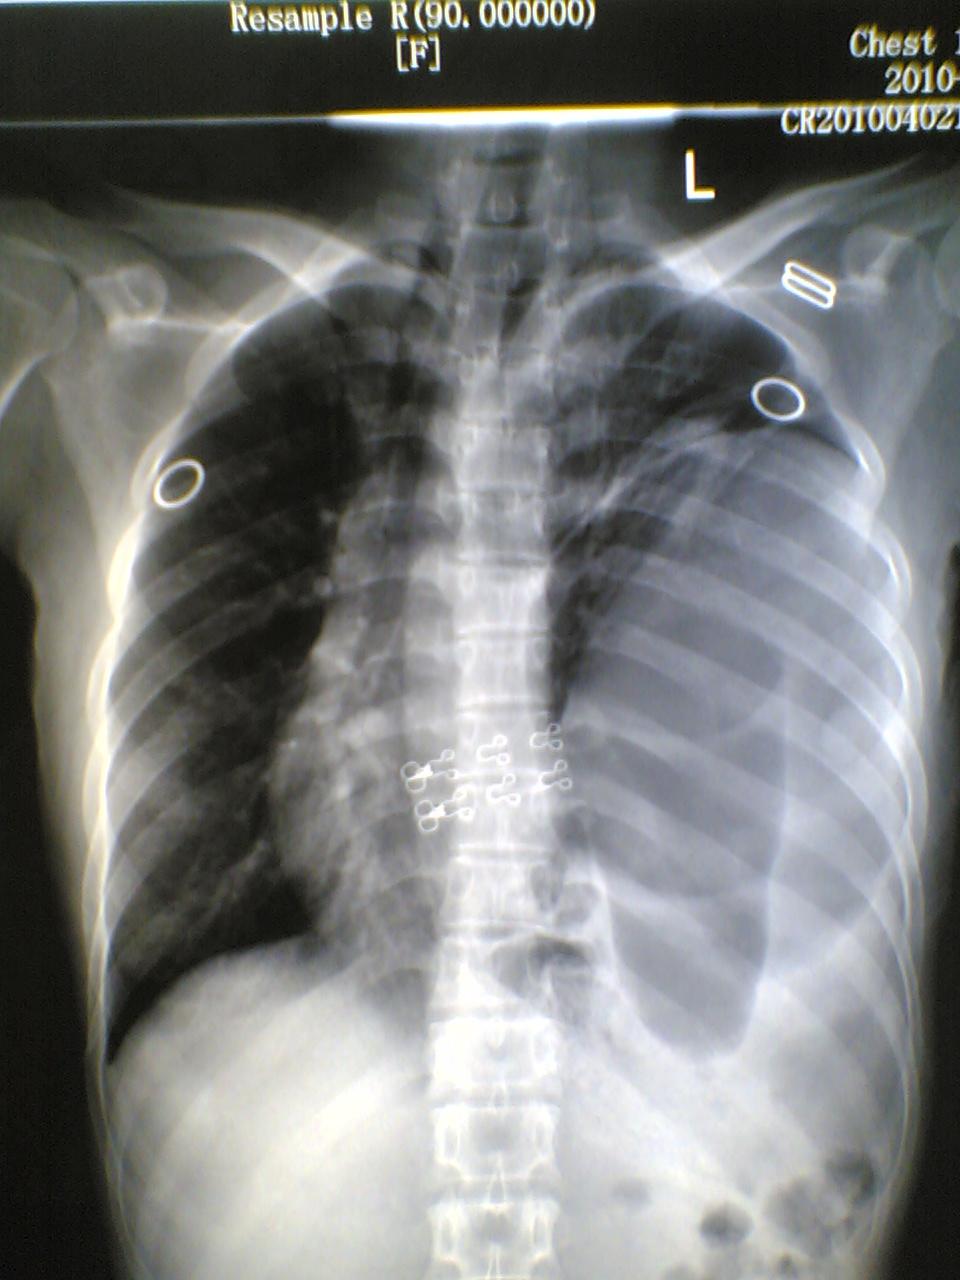

标题: X7060:女,40,呕吐一日,自觉上腹部不适,剑突下痛。 [打印本页]

标题: X7060:女,40,呕吐一日,自觉上腹部不适,剑突下痛。

膈疝?膈膨升?胃泡上是膈面还是肺组织?请各位老师多多指教(图像质量欠清,包涵)

1)考虑左侧膈疝。2)左下肺盘状肺不张。

左侧膈疝,伴胃扩张,左下肺膨涨不全(压缩所至)。

左侧膈疝,左下肺盘状不张。

1)考虑左侧膈疝。2)左下肺盘状肺不张。支持!应该做钡餐或透视进一步检查。